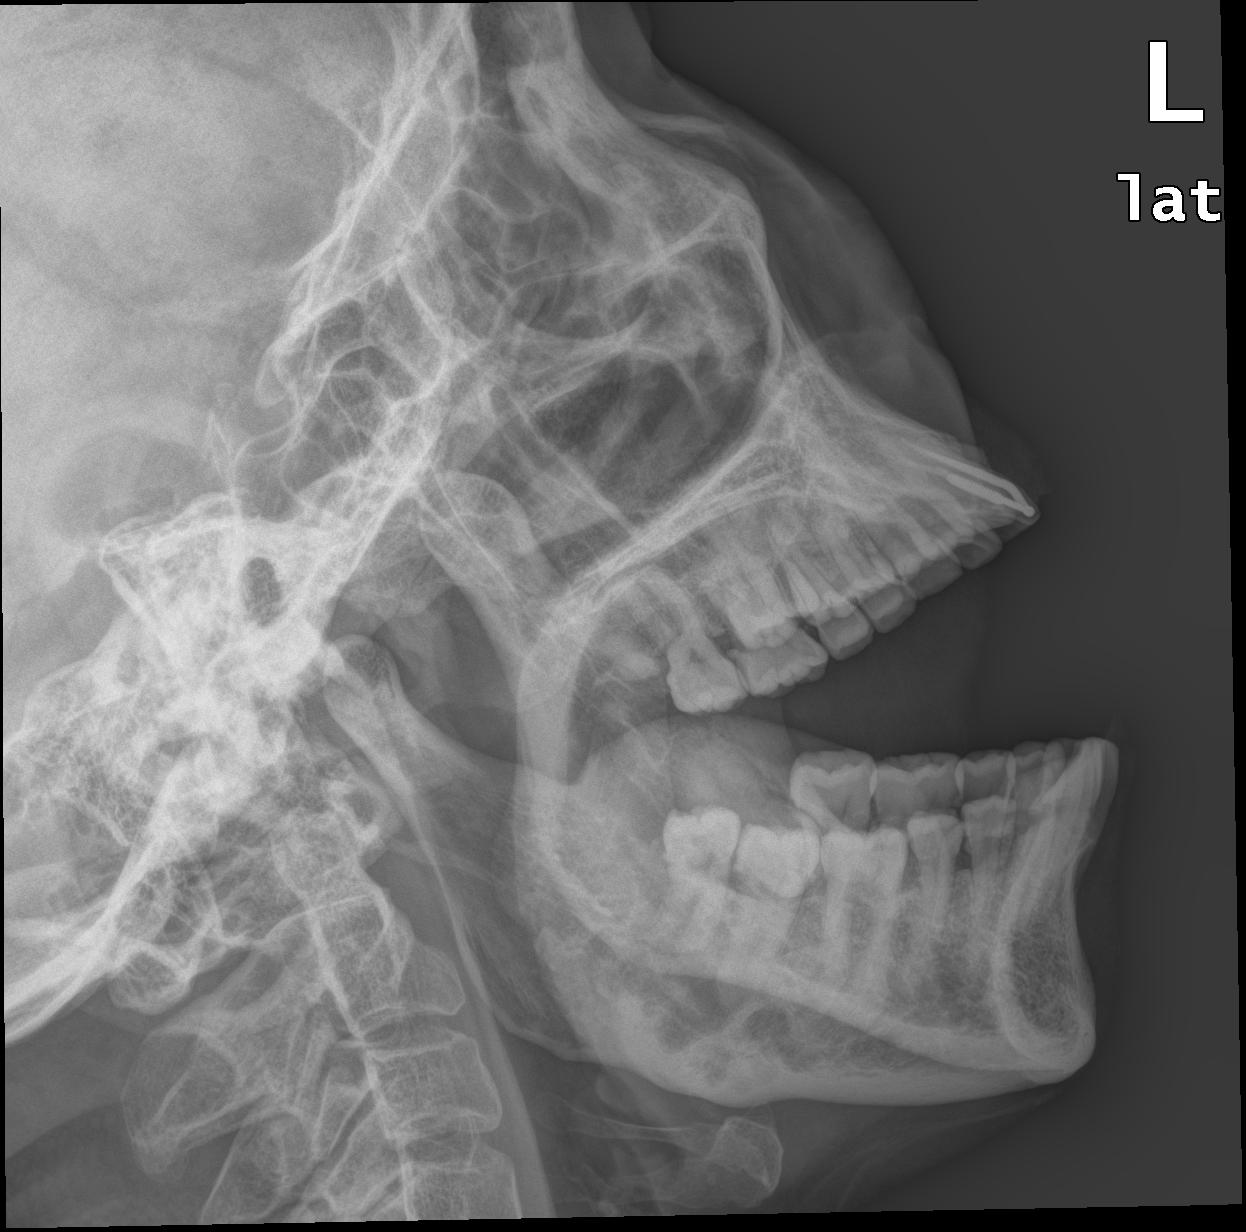

以下是引用hexue在2009-1-11 21:17:00的发言:[br]下颌骨体部骨质破坏区见间隔成多房且大小不一,边缘硬化增白.考虑为成釉细胞瘤.

以下是引用流星1234在2009-1-11 22:04:00的发言:[br]下颌体部多房样骨破坏囊状骨破坏,边缘硬化,局部略有骨膨胀,考虑成釉细胞瘤